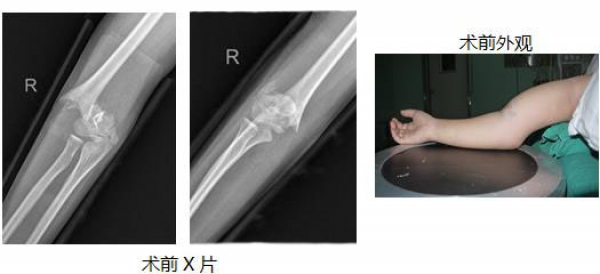

3.肱骨髁上骨折“零”切开。

华某某,12岁,男,完全移位的右肱骨髁上骨折,行肱骨髁上骨折“零”切开手术,术后恢复良好,不留疤,在门诊取内固定可立即离院。